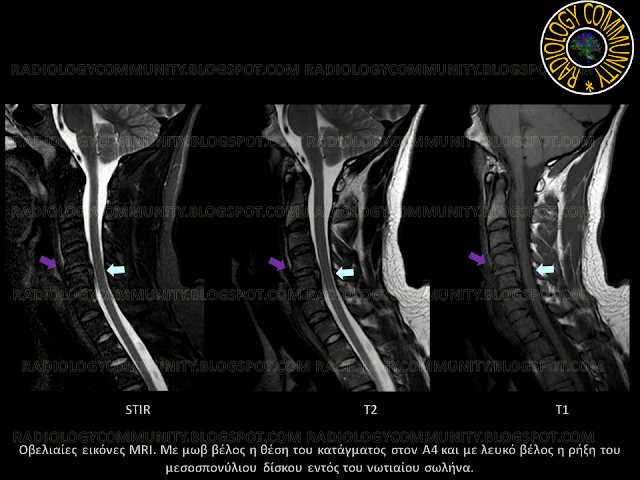

Ο ασθενής μεταφέρεται και στο τμήμα μαγνητικής τομογραφίας για τον έλεγχο του νωτιαίου μυελού. Πραγματοποιήθηκε πρωτόκολλο MRI ΑΜΣΣ που περιελάμβανε:

- T2W TSE σε οβελιαίο και εγκάρσιο επίπεδο

- T1W TSE σε οβελιαίο και εγκάρσιο επίπεδο

- STIR σε οβελιαίο επίπεδο

Επισημαίνεται η περιοχή του κατάγματος στο σώμα του Α4 καθώς και οι συνδεσμικές ρήξεις και η ρήξη του μεσοσπονδύλιου δίσκου Α4-Α5.